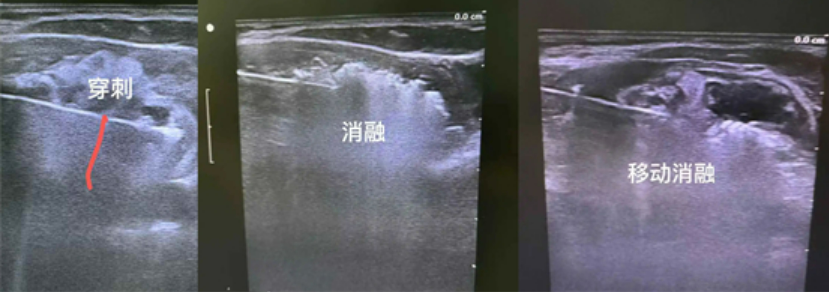

整個治療在超聲的引導下進行。B超掃描定位,首先以左側(cè)甲狀腺腫物為靶區(qū),B超引導下,用細針行穿刺活檢,送術中快速病理檢查,結(jié)果提示為未見癌細胞。因腫物巨大,術中還在甲狀腺與氣管間隙、與左側(cè)頸總動脈間隙、與食管間隙,注射生理鹽水進行水隔離處理,增大治療組織與周圍組織的間隙,保護周邊氣管、食管、頸部大血管、喉返神經(jīng)、喉上神經(jīng)等重要組織結(jié)構(gòu)。

隨后,以30W的功率開始微波消融。按由下至上,由內(nèi)至處,由深至淺的順序動態(tài)調(diào)整數(shù)微波刀位置,直至消融范圍覆蓋靶區(qū),拔除微波刀。就這樣,梅麗的甲狀腺結(jié)節(jié)被逐步“瓦解”。

微波消融巨大甲狀腺腫物